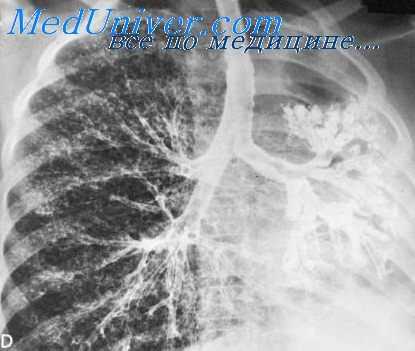

Существует три основных разновидности Б.: 1) двусторонняя — одномоментная или последовательная в процессе одного исследования, 2) односторонняя, 3) прицельная (сегментарная, направленная, селективная).

По характеру заполнения воздухопроводящих путей различают тугое и контурное контрастирование. При контурном контрастное вещество тонкой пленкой покрывает стенки бронхов, просвет которых остается свободным для дыхания. Оно более физиологично и полнее отражает детали внутренней поверхности бронхов. Для контурного контрастирования предложен метод аспирационной Б., когда контрастное вещество небольшими порциями подается на вдохе в просвет бронхиального дерева. Для исследования мельчайших разветвлений бронхиального дерева применяют так наз. концевую Б., для которой пригодны контрастные вещества типа желиодона, целиком удаляющиеся из легких.

Направление зонда, заполнение бронхов и их дальнейшее исследование выполняют под контролем обычной или телевизионной рентгеноскопии. В процессе Б. производят обзорные и прицельные рентгенограммы бронхиального дерева в различных проекциях. При необходимости применяют бронхотомографию.

Рентгенография бронхиального дерева при его контурном контрастировании на высоте глубокого вдоха, выдоха и форсированного выдоха позволяет судить о функциональных возможностях воздухопроводящих путей. Детальное изучение функции бронхов возможно с помощью рентгенокинематографии (см.) и видеомагнитной записи (см. Телевидение в медицине). Основное внимание следует уделять изменениям диаметра бронхов во время дыхательных проб. В норме во время вдоха бронхи расширяются и удлиняются, а при выдохе происходит уменьшение их диаметра и длины (рис. 4). При этом сохраняются ровные очертания бронхиальных стволов. Большое влияние на дыхательную подвижность бронхов оказывает тонус воздухопроводящих путей. При повышении тонуса наблюдается уменьшение амплитуды дыхательной подвижности стенок бронхов при общем сужении бронхиальных стволов. Возможны спазмы устьев бронхов, спастическая деформация воздухопроводящих путей, к-рая носит сегментарный характер и сохраняется в фазе вдоха. При гипотонии бронхов амплитуда дыхательной подвижности стенок бронхиальных стволов возрастает: на вдохе бронхи избыточно расширяются, а в фазе выдоха (форсированного выдоха) происходит резкое сближение стенок, т. е. формируется выдыхательный клапанный стеноз.